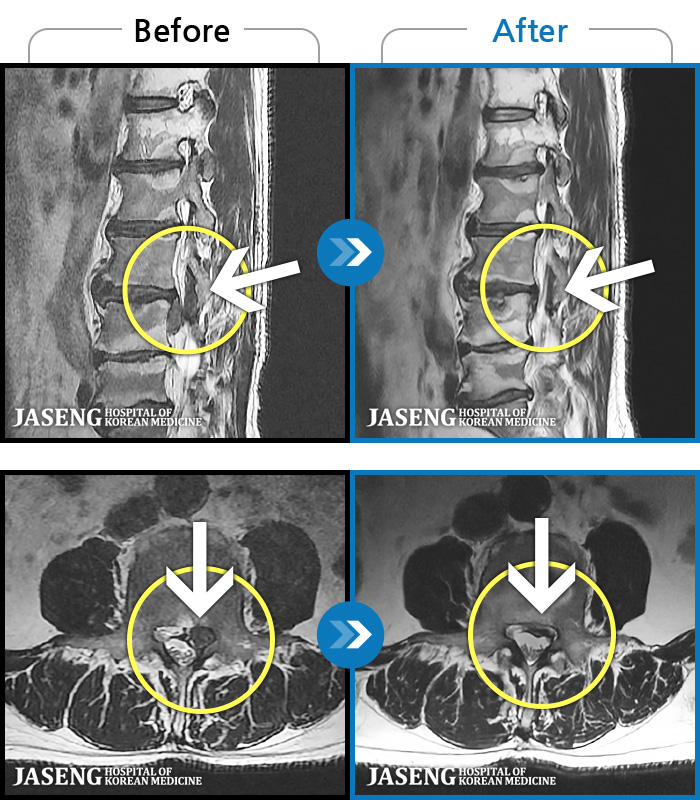

MRI ġ

1,301 MRI ũ ʸ Ȯϼ.